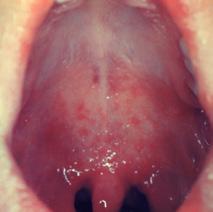

mucous membranes of the respiratory system like your nose and sinuses. Phlegm is a similar body product but is produced by the throat and lungs and tends to be thicker than mucus. White mucus and phlegm typically indicate a viral cause, such as influenza, while yellow and green mucus and phlegm point towards a bacterial origin, such as Streptococcus pneumoniae Congestion can also have non-pathogenic causes, including exposure to pollutants and allergens. Symptoms of congestion might include trouble breathing through the nose or a feeling of fullness in the face. Signs of congestion might include seeing nasal mucus coming out of a patient’s nose or listening for the distinct congested or nasally-toned voices that often accompany this condition.